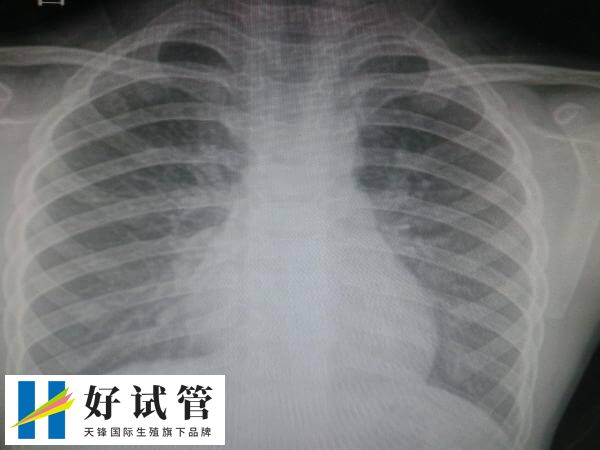

在进行试管婴儿前进行胸透,一般是为了排除肺部疾病,如肺结核、肺炎、肺部肿瘤等,以免不利于试管治疗期间的身体健康,其次胸部X光检查还可以了解心脏的基本情况,并查看胸廓情况,以预设后续试管婴儿助孕治疗的方案,从而确保整个试管婴儿过程的安全性。

患者做试管婴儿前期检查拍胸部x光,主要是排除肺部疾病的发生,如肺结核、肺炎、肺部肿瘤等疾病,以及胸部器官的基础疾病,bij这些疾病可能会影响试管婴儿的进程和孕妇的健康。

在进行试管婴儿前进行胸透(胸部X光检查),也可以评估心脏情况,比如可以评估心脏的大小和形态,了解心脏的基本情况,排除心脏疾病对妊娠的潜在影响。

胸透检查可以作为术前的常规检查项目,为后续的治疗和手术提供参考依据,确保整个试管婴儿过程的安全性。